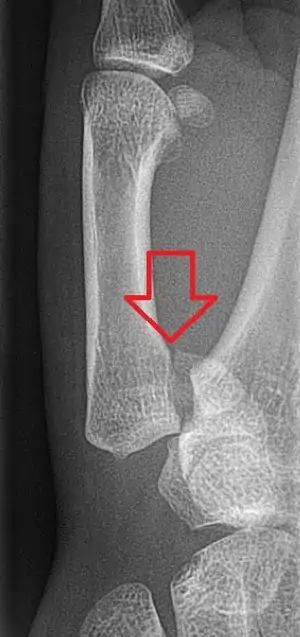

A Bennett fracture is a type of broken finger involving the base of the thumb, which extends into the knuckle joint.[4][1] Symptoms generally include thumb swelling and pain.[1] Associated injuries may include ulnar collateral ligament injury of the thumb or trapezium fracture.[1]

The cause is generally a force along the long axis of the thumb.[1] Diagnosis is supported by X-rays.[1] There is nearly always some degree of disruption of the carpometacarpal joint.[2]

The distal fragment of the first metacarpal bone possesses the majority of the articular surface of the first CMC joint. Unlike the proximal fracture fragment, strong ligaments and muscle tendons of the hand tend to pull this fragment out of its correct anatomical position.